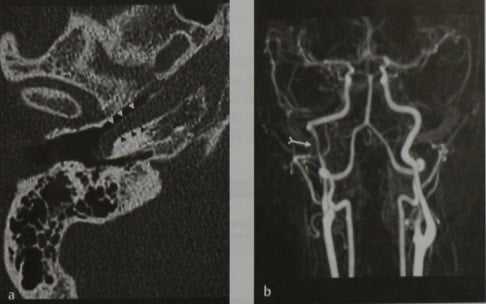

Аберрантная ВСА. КТ без усиления (костное окно), аксиальная проекция (а), МРА в М1Р-режиме с контрастированием (b) и ЦСА (с). Горизонтальный сегмент (наконечники стрелок) эктопической правой ВСА выступает в полость среднего уха без признаков кортикального покрытия (а). Вертикальный сегмент (раздвоенная стрелка) уже, чем на противоположной стороне (b, с), поскольку эктопический сосуд входит в каменистую кость через барабанный каналец.

Физиологический (а) и эктопический (b) варианты строения ВСА (цит. по : Lo et al; с изменениями).

a В норме каменистая часть ВСА состоит из вертикального и горизонтального сегментов. Нижняя барабанная артерия, отходящая от восходящей глоточной артерии, проходит через барабанный каналец и в области мыса (promontorium) образует анастомоз с сонно-барабанной артерией, которая, а свою очередь, проходит через сонно-барабанный канал.

b При аплазии шейного сегмента ВСА компенсация кровообращения осуществляется за счет увеличения интенсивности кровотока по расширенным нижней барабанной и сонно барабанной артериям. Вертикальный сегмент каротидного канала при этом отсутствует.